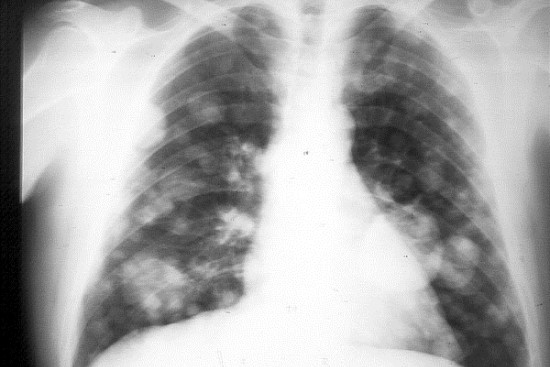

El cáncer de pulmón se origina cuando las células comienzan a reproducirse de manera descontrolada, forman un tumor y se trasladan a otras partes del organismo donde crecen y crean nuevos tumores que remplazan al tejido normal, refirió.

«Generalmente comienza en las células que envuelven los bronquios, los bronquiolos y/o los alvéolos», especificó Nolasco Ramírez.